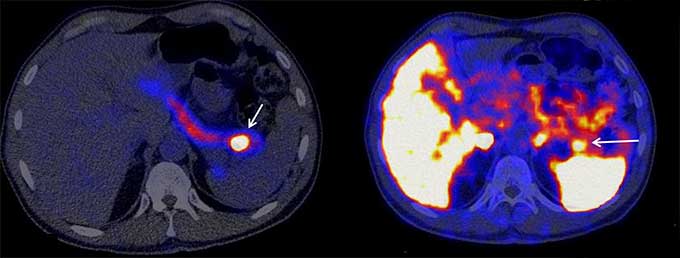

To test their new tracer, the researchers recruited 69 people who had been biochemically diagnosed as having low blood sugar due to excessive insulin. Each underwent all standard imaging tests as well as the new exendin-4 PET scan, which led to 53 individuals undergoing surgery to remove suspected tumors. Out of those 53 confirmed cases, the tumor showed up in 50 of the exendin-4 PET scans, as opposed to just 35 of the standard PET scans. In seven cases, the exendin-4 scans detected insulinomas while standard PET, CT and MRI imaging picked up nothing.

The exendin-4 was also very good at picking up only the insulinomas in the scan, with less background noise compared with currently used PET scans, and had fewer side effects on the patients compared to previous versions of the exendin-4 radiotracer.